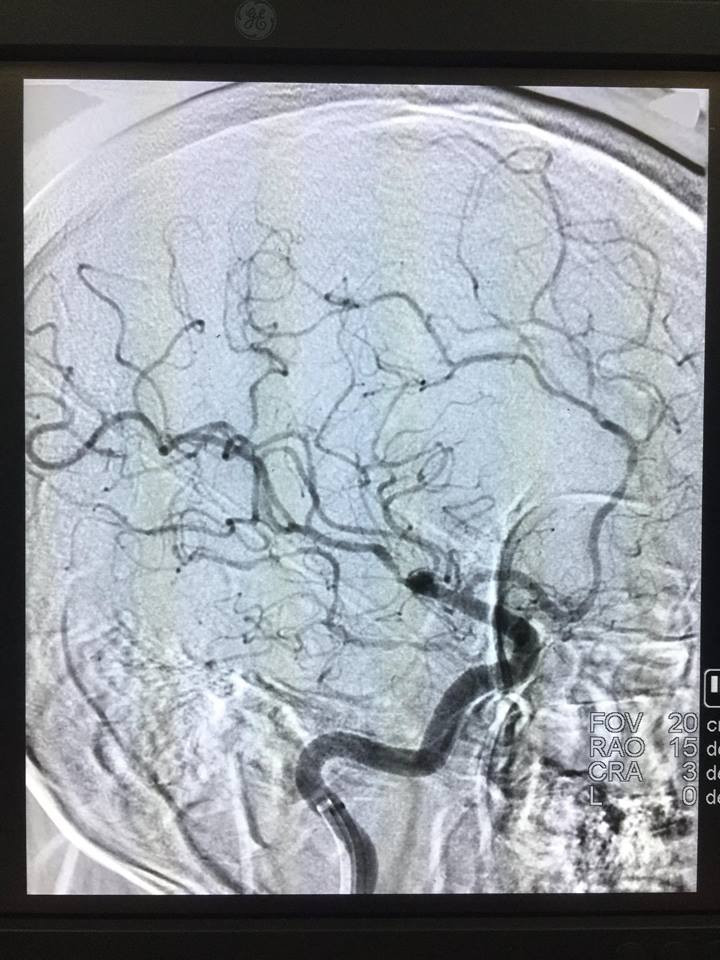

Một ê kíp các bác sỹ khoa Chẩn đoán hình ảnh và Khoa Hồi sức tích cực - Chống độc đã nhanh chóng hội chẩn và chỉ định dùng thuốc tiêu huyết khối kết hợp với can thiệp mạch máu não bằng phương pháp lấy huyết khối bằng dụng cụ cơ học. Chỉ sau 30 phút can thiệp, các bác sỹ đã lấy được nhiều mảnh huyết khối và động mạch não được tái thông hoàn toàn và trở lại trạng thái bình thường.

Bác sỹ Trương Quang Lục - Khoa Chẩn đoán hình ảnh, Bệnh viện đa khoa tỉnh Phú Thọ cho biết: "Người bệnh bị đột quỵ não vào giờ thứ 2 từ khi khởi phát triệu chứng. Người bệnh được chỉ định dùng thuốc tiêu huyết khối kết hợp với can thiệp mạch máu não bằng phương pháp lấy huyết khối bằng dụng cụ cơ học. Đến ngày thứ 5 sau can thiệp, người bệnh đã tỉnh táo, nói chuyện bình thường, sức khỏe dần ổn định".

Phương pháp can thiệp mạch não bằng dụng cụ cơ học là một trong những kỹ thuật khó, đòi hỏi chuyên môn sâu. Hiện nay mới chỉ triển khai được ở một số bệnh viện tuyến trung ương. Đây là ca can thiệp mạch não thứ 6 thành công tại Bệnh viện đa khoa tỉnh Phú Thọ, mang đến nhiều cơ hội cho người bệnh bị đột quỵ não.